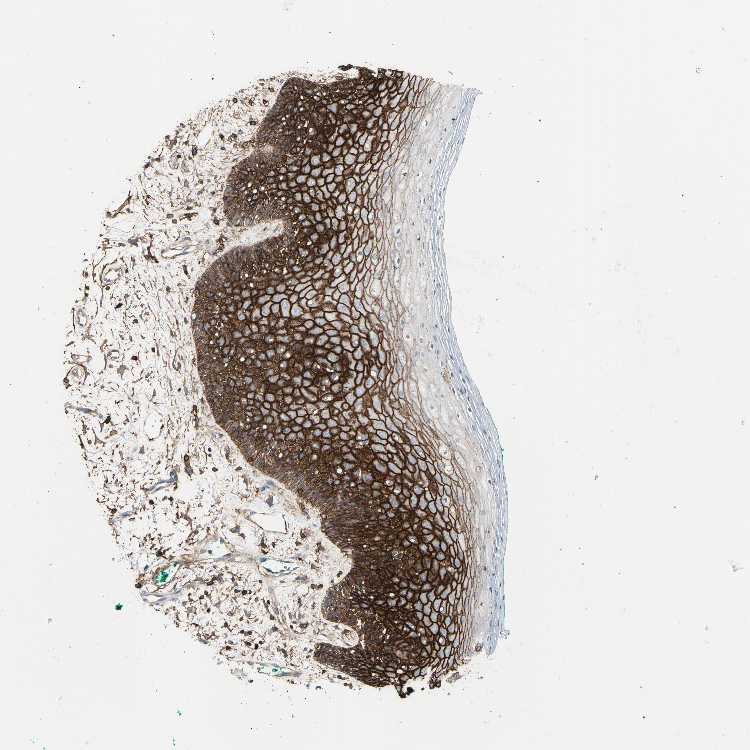

TISSUE PRIMARY DATA ORAL MUCOSA Show tissue menu

Oral mucosa

ORAL MUCOSA - Expression summary

ORAL MUCOSA - Antibody stainingi

Antibody staining in the annotated cell types in the current human tissue is reported as not detected, low, medium, or high, based on conventional immunohistochemistry profiling in selected tissues. This score is based on the combination of the staining intensity and fraction of stained cells.

Each image is clickable and will lead to virtual microscopy that enables deeper exploration of all samples and also displays staining intensity scores, fraction scores and subcellular localization as well as patient and tissue information for each sample.

Antibody HPA005785Antibody CAB000112Antibody CAB000316

Squamous epithelial cells HighLowHigh